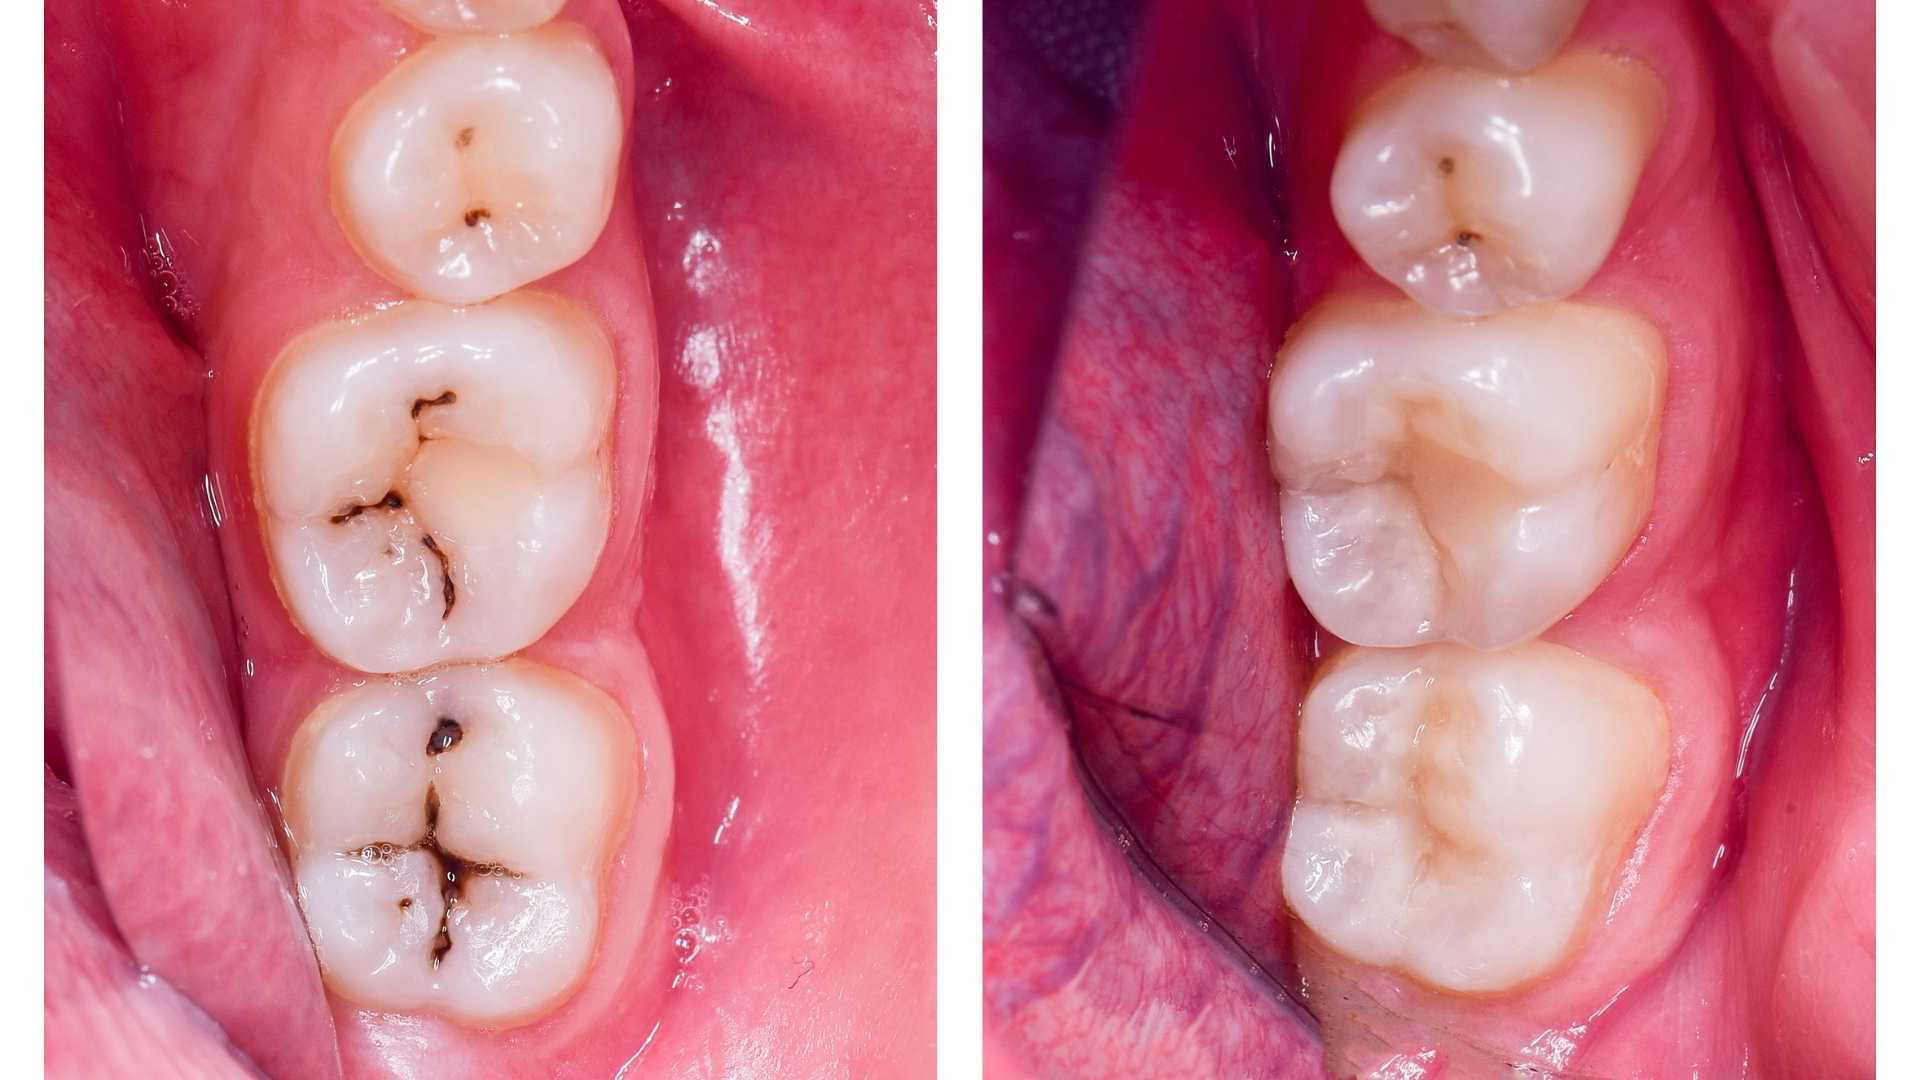

Cavities are small holes in the teeth that form after a tooth has become permanently damaged. While cavities may seem like a major dental problem, they can easily be repaired with a dental filling. Nothing gives us more pleasure than being able to conserve your natural teeth and help them remain healthy for life. At Sood Dental Care and Implant Centre, preservation of your natural teeth is our aim. This branch of specialization includes “fillings” in simple terms. Be it a chipped tooth, a decayed tooth or one with an old filling, we have a range of newest and most advanced materials to give you a filling that will help your tooth regain its lost health. Our Dentists will help fill the gap and protect your teeth from further decay.

At Sood Dental Care and Implant Centre we mainly use Tooth Coloured Fillings, be it Biocompatible Cements or Composite Resin (aka Laser Fillings in Layman’s terms).These teeth colored filling materials are cosmetic as well as strong to bear the chewing forces. Also the fillings are done under magnification to ensure the cavity is properly sealed and prevent future secondary decays in the tooth.

As the tooth starts to decay you might feel few physical symptoms like- food getting stuck in the holes in teeth, you might feel some chipped off areas with your tongue, and there might be some dark spots on the teeth.